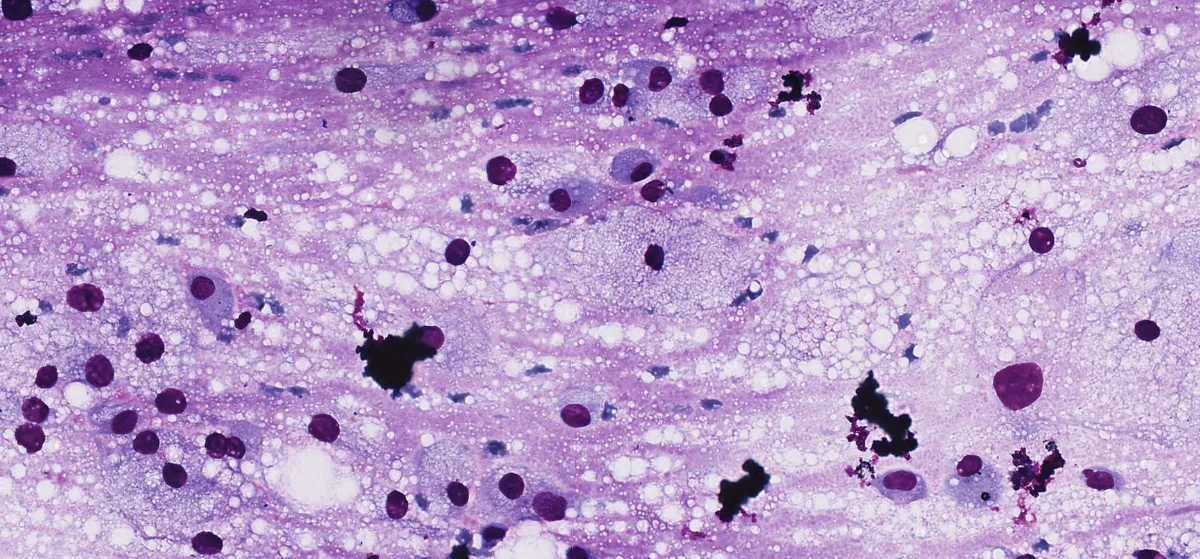

Paciente femenina de 15 años sin antecedentes. Presenta una masa en región cigomática derecha de 3 cm, firme, no dolorosa, sin signos inflamatorios, aparecida en el contexto de un tratamiento de ortodoncia. La resonancia magnética sugiere una lesión inflamatoria, pero tras tratamiento antibiótico sin mejoría, se realiza PAAF intraoral. La citología muestra células atípicas con características lipoblastoides, abundante fondo mixoide y vascularización capilar plexiforme. Se observan mitosis atípicas y positividad para Vimentina y Adipofilina. No se detectan translocaciones de DDIT3 ni PLAG1, ni amplificación de MDM2.

Diff-Quik Cito 1

Diff-Quik Cito 2